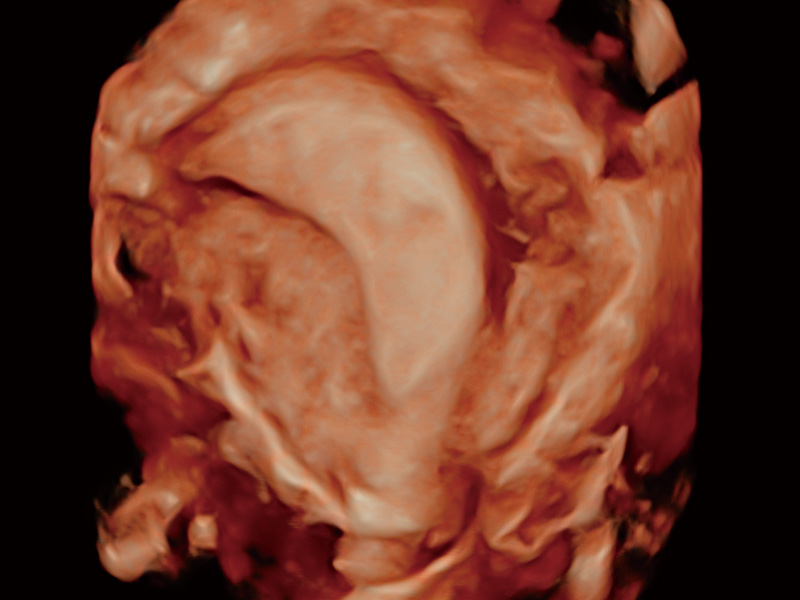

腔内三维成像技术获得显著提升,超大扇角在满足日常基础扫查的同时,支持卵泡自动测量及多种三维渲染模式,为您提供更多的诊断信息,尤其是在子宫畸形的诊断,内膜及肿瘤占位观测中起到了重要的作用。

卵巢多囊样改变

单角子宫